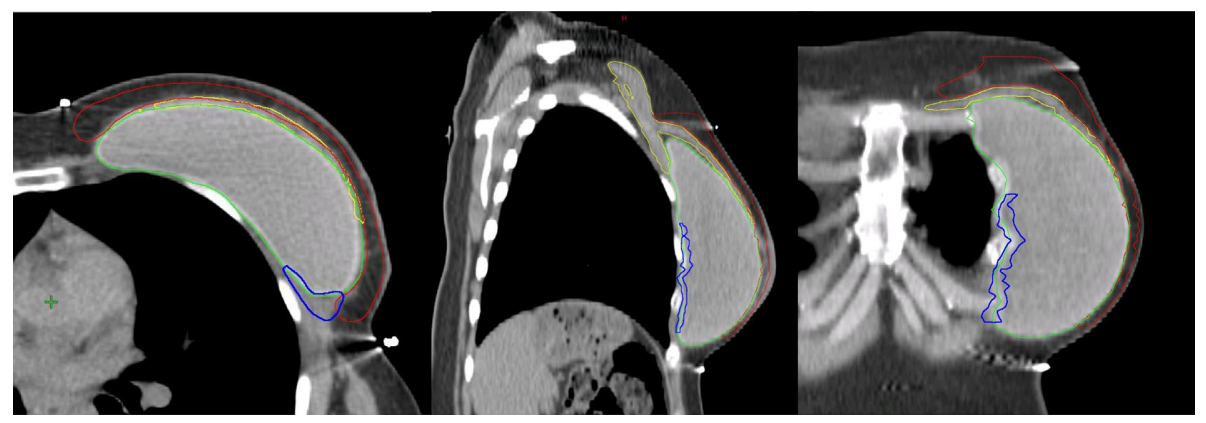

Hình 4c. CTVp_chestwall với phần trước (Đỏ) và sau (Xanh biển) trong trường hợp túi độn trước cơ ngực (Xanh lá cây). Cơ ngực (Vàng)

Sau IBR-i sử dụng túi độn trước cơ ngực, CTVp_chestwall bao gồm 2 phần phân chia bởi túi độn:

(1) Phần trước: Giữa da và túi độn, chứa đựng mạng lưới bạch huyết dưới da và mô tuyến tồn dư (Nếu có) (Hình 4C, thể tích giới hạn bởi đường viền đỏ);

(2) Phần sau: Giữa túi độn và cơ ngực/thành ngực, chứa đựng mô tuyến tồn dư (Nếu có) (Hình 4c, thể tích giới hạn bởi đường viền xanh biển); chỉ trở thành một phần của CTV trong các trường hợp có các yếu tố khối u bất lợi (Bảng 1).